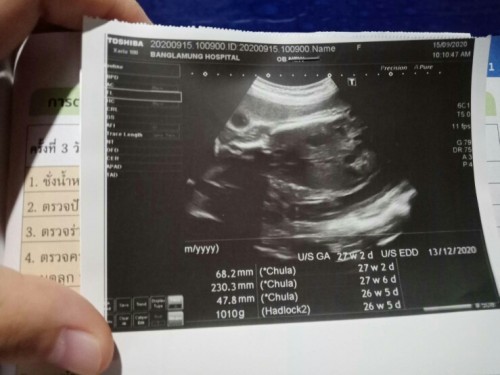

ขอสอบถามแม่ๆหน่อยค่ะรูปนี้คืออะไรหรอคะดูไม่ออกไม่ได้ถามหมอด้วยค่ะ#ท้องแรกคะ #ขอบคุณสำหรับคำตอบค่ะ

น่าจะช่องท้องนะคะ ตรงจุดดำๆคือกระเพาะและไตค่ะ